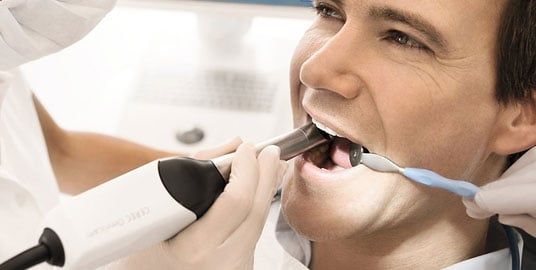

We use a highly-sensitive precision wand to digitally scan the section of your mouth where a dental restoration will be placed. As the wand scans the area, it builds a virtual model of your mouth on a screen right in front of your eyes. You and your doctor can fine-tune the area until the virtual model represents your mouth exactly.

CEREC Omnicam

CEREC Omnicam is optimized for powder-free scanning of natural tooth structures and gingiva. Simply place the camera over the relevant area and the scan starts automatically. The elimination of a powder coating means that the scanning process is faster and easier. Full-arch and half-arch scans can now be performed more conveniently and quickly than ever before.

2. Next, using our state-of-the-art CEramic REConstruction (CEREC) system, we will digitally scan the section of your mouth that has been prepared for the crown. This is done by using a special wand that can be easily positioned in your mouth to ensure an extremely accurate digital representation of the restoration area.